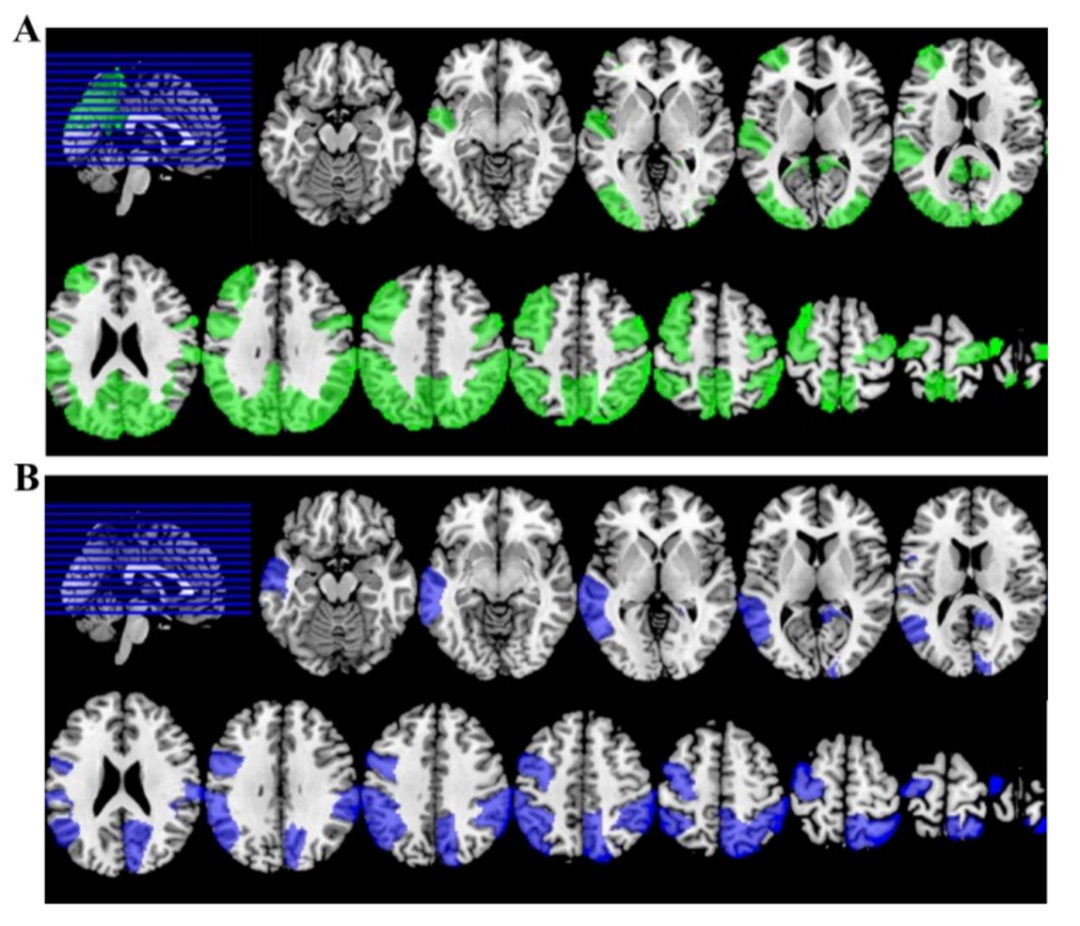

(一)题目:Free water DTI for evaluating gray matter microstructure in major depressive disorder: A preliminary study

内容简介:本研究使用自由水矫正的扩散张量成像方法(fw-DTI),研究重度抑郁症(MDD)患者的大脑皮质微结构变化。fw-DTI相对于传统DTI,可以矫正各项同性的自由水(比如脑脊液)对结果的影响,具有更高的灵敏度。结果发现,MDD患者的多个脑区皮质微结构出现异常,并且患者的抑郁程度与左后扣带回的自由水矫正平均扩散系数有显著的正相关。

图中展示的是:MDD患者中,全脑大部分皮质的自由水校正平均扩散系数(MD)和轴向扩散系数(AD)出现明显的异常。